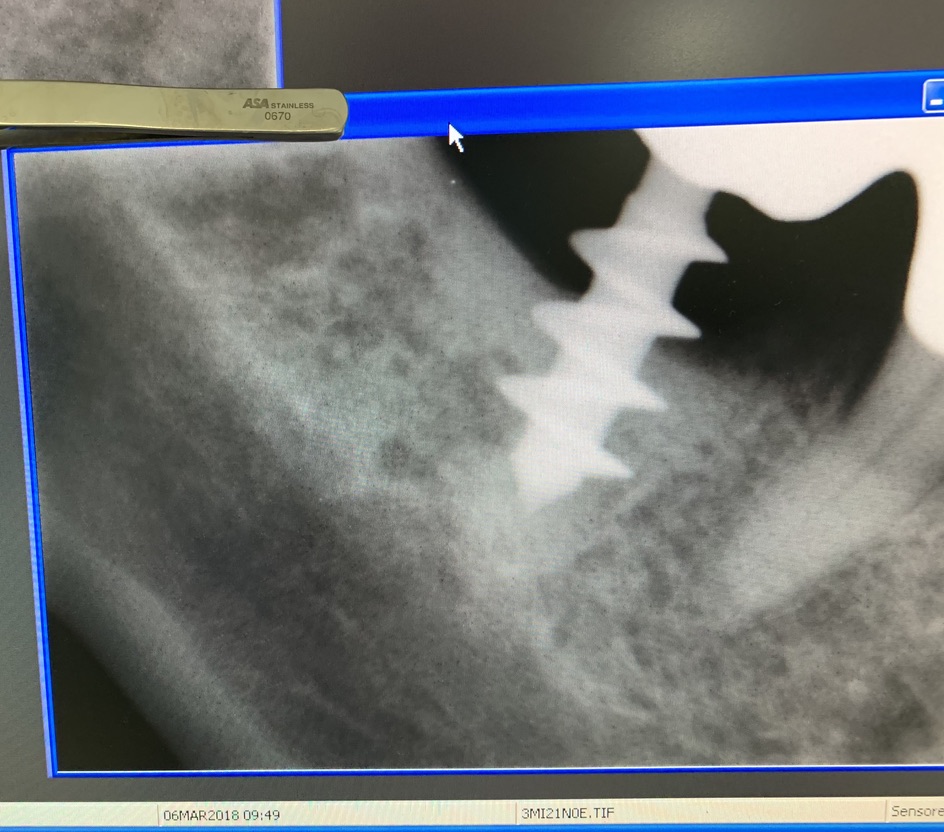

Original form of the Tramonte implant. 5 mm diameter with 3 threads. Stem diam. 2.1 mm. Neck diam. 2 mm x 5 mm in length. Grade 2 titanium. Grade 2 allowed the need to bend the implant neck to improve parallelism. It is an immediate post-extraction implant. Therefore, in the same session, extraction, boring, tapping and implant insertion. Immediately followed by monconization and the preparation of temporary crowns in light occlusion. The radiographs provided show the situation since 2010. The emergence of the thin neck favors the formation of a dense gingiva sleeve that protects against peri implantitis. The wide threads radiate the occlusal load away from the implant body, favoring the formation of a more homogeneous bone.